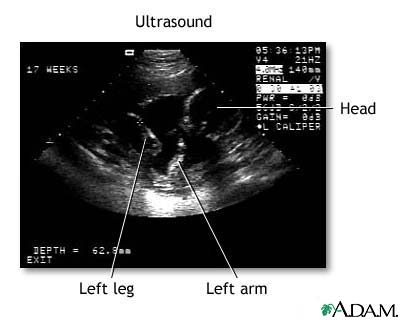

Ultrasound, normal fetus- ventricles of brain

This is a normal fetal ultrasound performed at 17 weeks gestation. The development of the brain and nervous system begins early in fetal development. During an ultrasound, the technician usually looks for the presence of brain ventricles. Ventricles are spaces in the brain that are filled with fluid. In this early ultrasound, the ventricles can be seen as light lines extending through the skull, seen in the upper right side of the image.